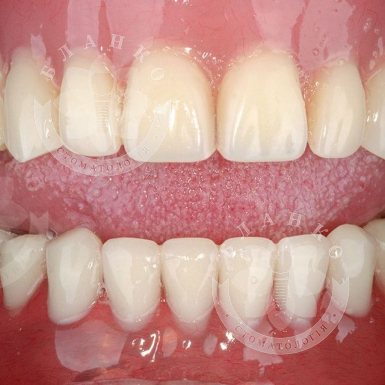

植牙 —這是修復缺牙的現代且可靠的解決方案。在Blanco牙科診所,我們提供交鑰匙牙種植,這意味著全方位的服務 —從診斷到安裝牙冠,沒有隱藏費用或意外開支。